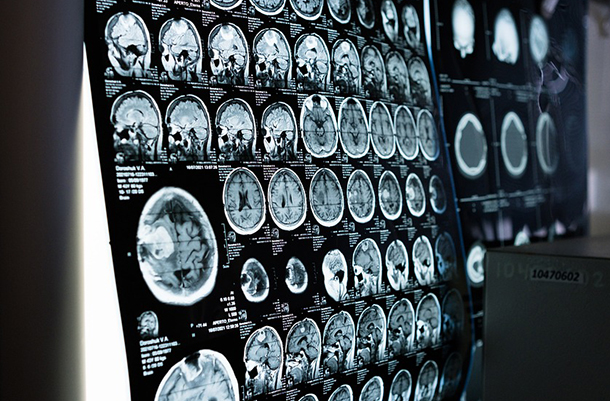

알츠하이머 환자는 짜증나고, 동요하고, 불안하기로 악명이 높다. 새로운 연구에 따르면 뇌의 염증이 알츠하이머병과 관련된 분노, 불안을 유발할 수 있는 것으로 나타났다.

환자의 뇌 스캔과 임상 평가에서는 뇌의 면역 반응으로 인한 염증이 수면 장애 및 동요를 포함한 다양한 정신과적 증상과 밀접한 관련이 있는 것으로 나타났다.